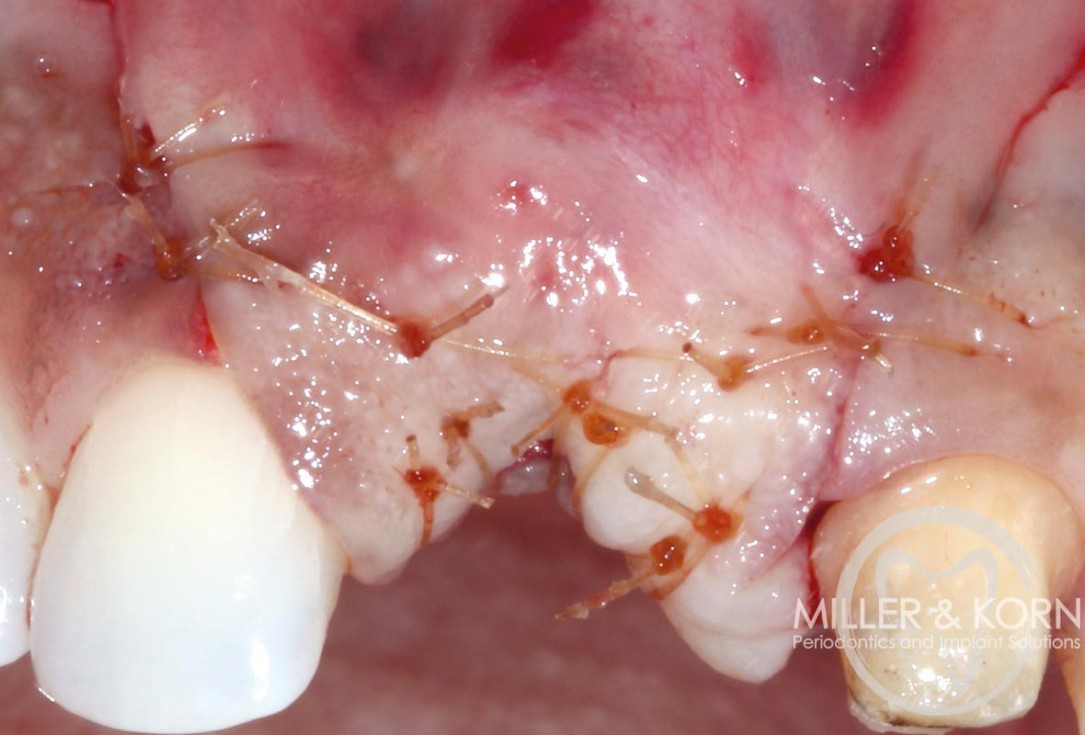

15/22 - Closing the flap.Immediate implant placement and regeneration of ridge using an allograft bone ring and Jason® membrane - Drs. Miller and Korn